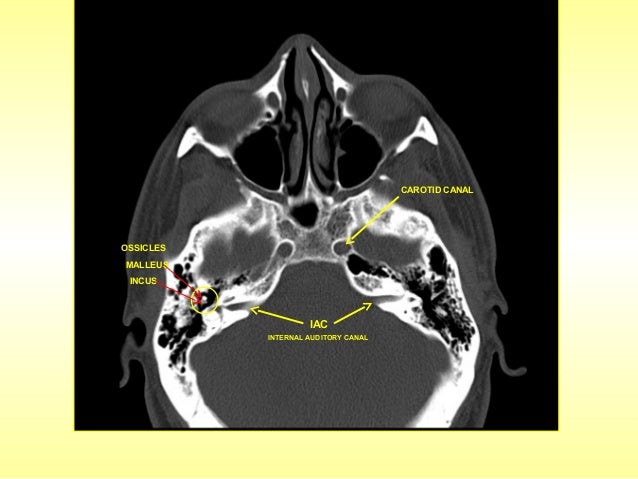

Ct skull base anatomy. You can however go directly to any section using the links below. B axial ct image with color coded overlay shows the skull base bones. The skull base can be evaluated by computed tomography ct which will demonstrate the bony structures of the skull base with its foramina and fissures for vessels and cranial nerves the temporal bone and sinonasal cavities.

5 internal occipital protuberance. 4 mastoid air cells. 3 anterior clinoid process.

Ct anatomy of skull base. Blue central skull base csb purple posterior skull base teal anterior skull base asb. Foramina of the skull base and the structures that pass through them.

Cranial foramina for further details. A axial three dimensional reconstructed ct image with color coded overlay shows the skull base sections. Ct anatomy of skull base.

The base of the skull is perforated by numerous foramina which allow vessels and nerves to pass through the base of the skull allowing the intracranial cavity to communicate with the rest of the body see main article. Skull ct anatomy the sagittal suture is the line where the right and left parietal bone are in contact. A noncontrast sinus or skull base ct which covers the mastoids temporal bone and entire skull base is recommended and intravenous contrast is not usually necessary as the mri will provide soft tissue detail.

Ct is more sensitive in detecting fibro osseous skull base lesions calcification and sclerosis. The module interface is meant to mimic a radiology workstation with adjacent image scrolling via arrow keys and or mouse wheel button. Navigating the skull base identify the petro occipital fissure to navigate the major structures of the skull base.